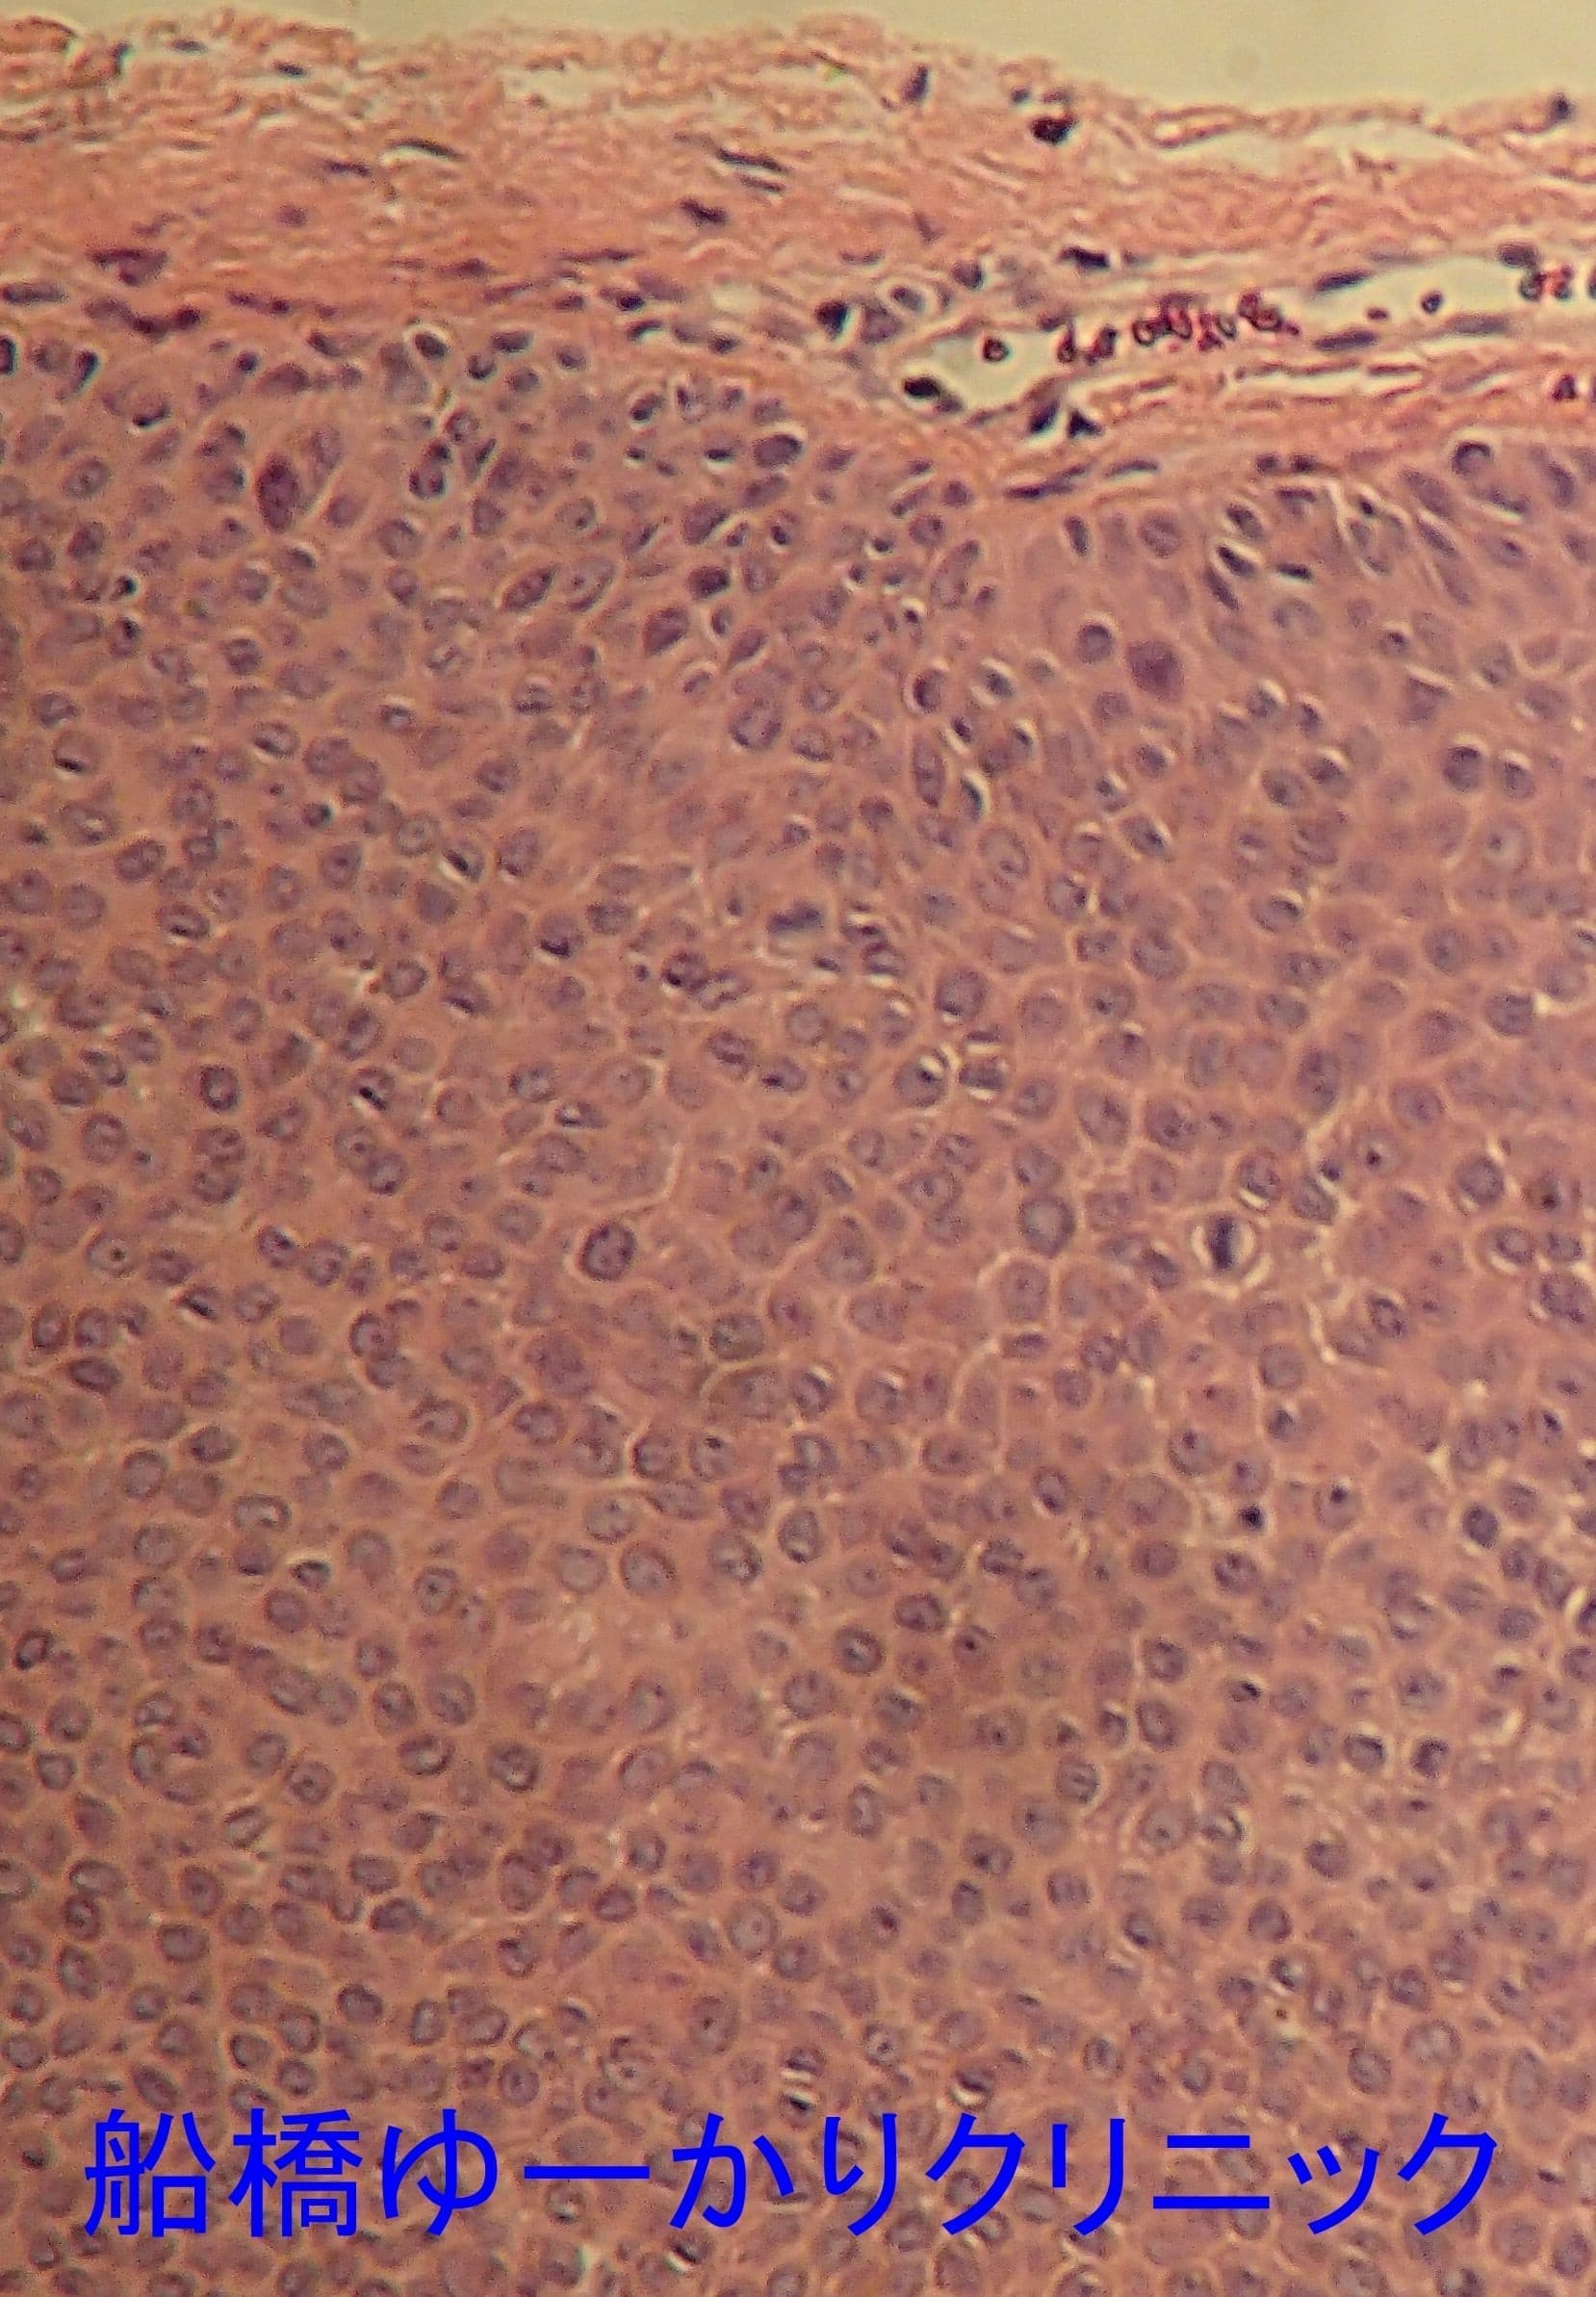

病理組織

汗管腫

母指に発生したしこり。予想外の組織で、汗管腫でした。

上腕のしこり。やや盛り上がって、薄い赤みがあります。エコーでは境界不明瞭な不均一な低エコー像。皮膚を紡錘形に切除し、皮下腫瘍を摘出しました。病理組織は皮膚線維腫でした。